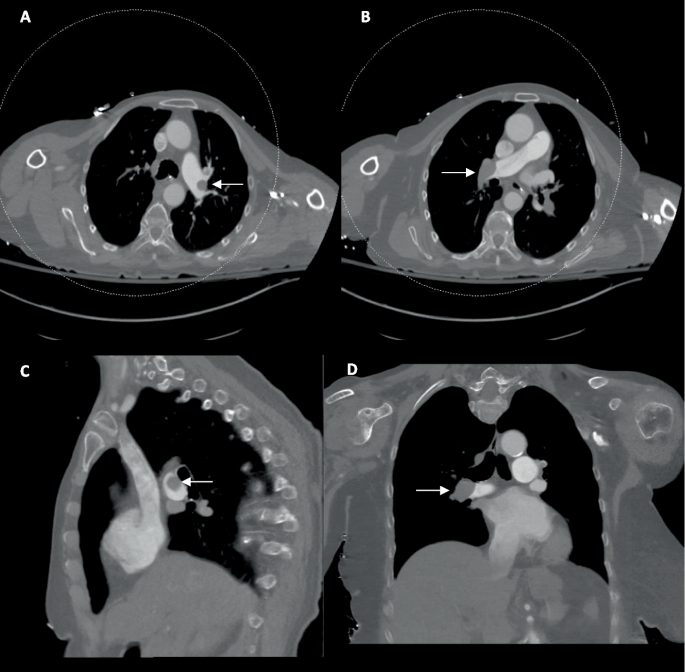

图3

A 导管被撤回至下腔静脉。B 注入造影剂。CF 心脏左侧和主动脉弓出现早期显影,进一步提示可能存在PFO